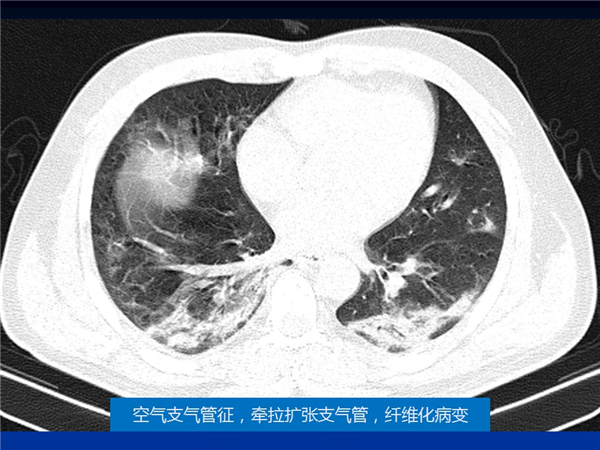

【病例分享】新型冠狀病毒感染肺部CT影像4例(常德市第一人民醫(yī)院)

幻燈片5.jpg